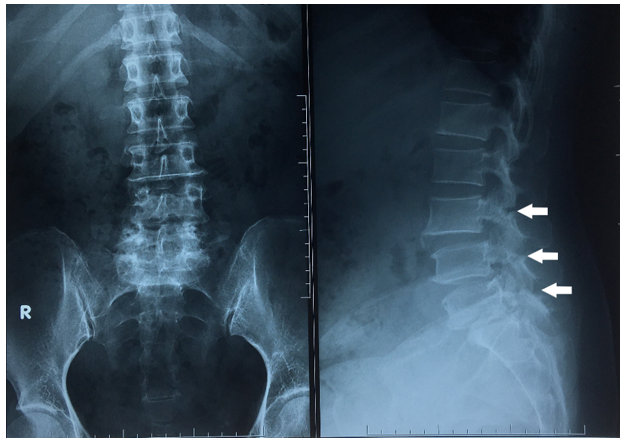

Hình 1. Xquang cột sống thắt lưng thẳng – Trái, nghiêng – Phải: trượt đốt sống ba tầng L3-L4, L4-L5, L5-S1 ra trước độ I, khuyết eo đốt sống L3, L4, L5

Bệnh nhân nữ 49 tuổi vào viện vì đau thắt lưng âm ỉ trong hơn 8 tháng nay, gần đây triệu chứng đau tăng dần đặc biệt khi đứng và đi lại kèm co cứng vùng cột sống thắt lưng làm hạn chế vận động nhiều. Khám thực thể: đau dọc theo rễ thần kinh S1, điểm JOA và VAS cho đau thắt lưng là 8 và 10, dấu hiệu bậc thang dương tính, Lasègue dương tính 30 độ chân phải, 50 độ chân trái, X quang cột sống thắt lưng (Hình 1) và cộng hưởng từ cột sống thắt lưng cho thấy khuyết eo cột sống thắt lưng ba tầng ở L3-L5 với trượt nhẹ thân đốt sống L3, L4, L5 ra trước phối hợp phình lồi đĩa đệm ga chèn ép rễ thần kinh S1 hai bên trong ống sống (Hình 2) và thoái hóa đốt sống đĩa đệm đa tầng, đốt sống L3, L5, S1 thoái hóa MODIC II, biến dạng nhẹ đường cong sinh lý. Điều trị nội khoa bằng thuốc giảm đau, chống viêm, và giãn cơ không cải thiện. Bệnh nhân trượt đốt sống đa tầng do khuyết eo từ L3-L5 và có triệu chứng đau theo rễ thần kinh S1 nên chúng tôi đã quyết định tiến hành phẫu thuật PLIF: cố định cột sống bằng vít qua cuống tại L4-S1 và đặt mảnh ghép liên thân sống (PEEK) tại L5-S1.